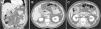

A. Corte coronal, presencia de cambios inflamatorios pericolecísticos (punta de flecha) y un flemón pericólico (flecha). B. Corte axial, cambios inflamatorios perivesiculares, estriación de la grasa a este nivel, datos que pudieran indicar un cuadro de colecistitis aguda. C. Corte axial, engrosamiento de la pared del colon del ángulo hepático y estriación de grasa pericolónica, con enfermedad diverticular activa.

El paciente presentó hemoglobina de 12.4g/dl, plaquetas de 336,000cél/mm3, leucocitos de 16,400cél/mm3 y pruebas de función hepática sin alteraciones. Se realiza ultrasonido de abdomen superior, donde se evidencia la vesícula biliar distendida con lodo biliar, con ausencia de litos, pared de 3mm, colédoco en 5.5mm y el resto de los parámetros dentro de la normalidad. Por continuar con el dolor, se decidió realizar una tomografía computarizada (TAC) con contraste intravenoso (fig. 1). No se podía distinguir con exactitud si lo observado en la TAC era a causa de enfermedad colónica o de la vesícula biliar. Se decide inicialmente manejo conservador con reposo intestinal, analgésicos y antibioticoterapia de doble esquema con ciprofloxacino y metronidazol durante 7 días. Debido a la mejoría clínica se decide su alta con tratamiento por vía oral con los mismos antibióticos durante otros 7 días. Seis semanas después se realiza una TAC de control, que evidencia la resolución completa de la inflamación perivesicular y pericolónica. El paciente fue visto asintomático al mes y 12 meses después de su cuadro inicial.